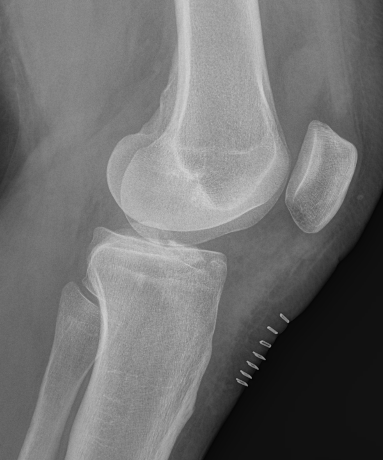

Meyers & McKeever classification

Type I: Undisplaced

Type II: Partially displaced with anterior portion hinged

Type III: Completely Displaced

Zaricznyj Type IV: Comminuted

Type II / III

Type II Type III

Type IV